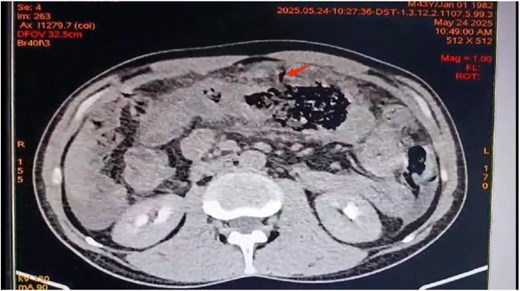

A contrast-enhanced abdominal CT showed Balthazar E pancreatitis with peripancreatic necrosis, thickening of the transverse colon and first jejunal loop, and sealed colonic perforation. Perisplenic and perihepatic fluid collections were noted, with no free air (Figs 1 and 2).

Axial view of contrast-enhanced abdominal CT scan revealing Balthazar E pancreatitis with peripancreatic necrosis.